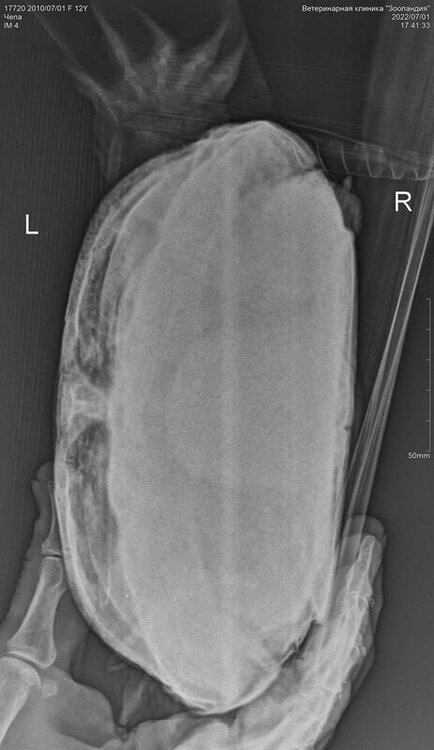

13. 12 лет, вес 1013 гр, ничего не ест, слабая, почти всегда находится на суше, открывает рот и надувает шею шариком, припухла, чешет нос лапкой, голова чаще лежит на островке. Болеет неделю, но вялость стала проявляться чуть раньше. Нашла в городе вет. врача, в сферу интересов которого входит лечение рептилий (не герпетолог), но ближайшая консультация возможна только через неделю. Чтобы не терять время, сделала рентген, уколола один раз 0,5 мл элиовита в мышцу ягодицы и через день колю борглюконат кальция 1 мл подкожно в бедро.

Вам тут нужно брать онлайн консультацию у герпетолога - у наших в телеграмм канале стоит 300р, оплата после консультации. Потому что из того, что я вижу - у черепахи практически полностью пережаты лёгкие и тут лечить должен врач. К сожалению я ничем помочь не смогу, потому что всё серьёзно.